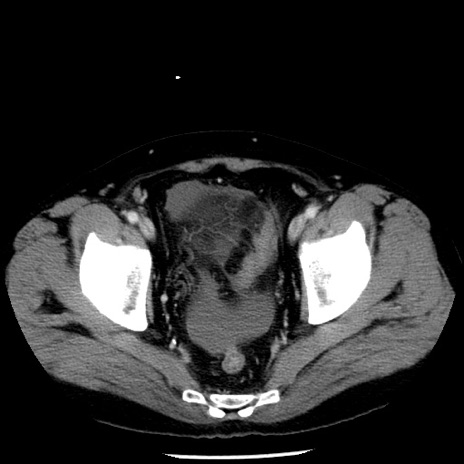

症例29(横断像)

【症例】40歳代男性

【現病歴】2日前から胃痛あり。徐々に周期的な激痛に変化した。本日になっても激痛があるため受診。

【身体所見】意識清明、BT 38-39℃台あり、腹部:膨満、やや硬、右下腹部に圧痛あり。

【データ】WBC 8500、CRP 23.26